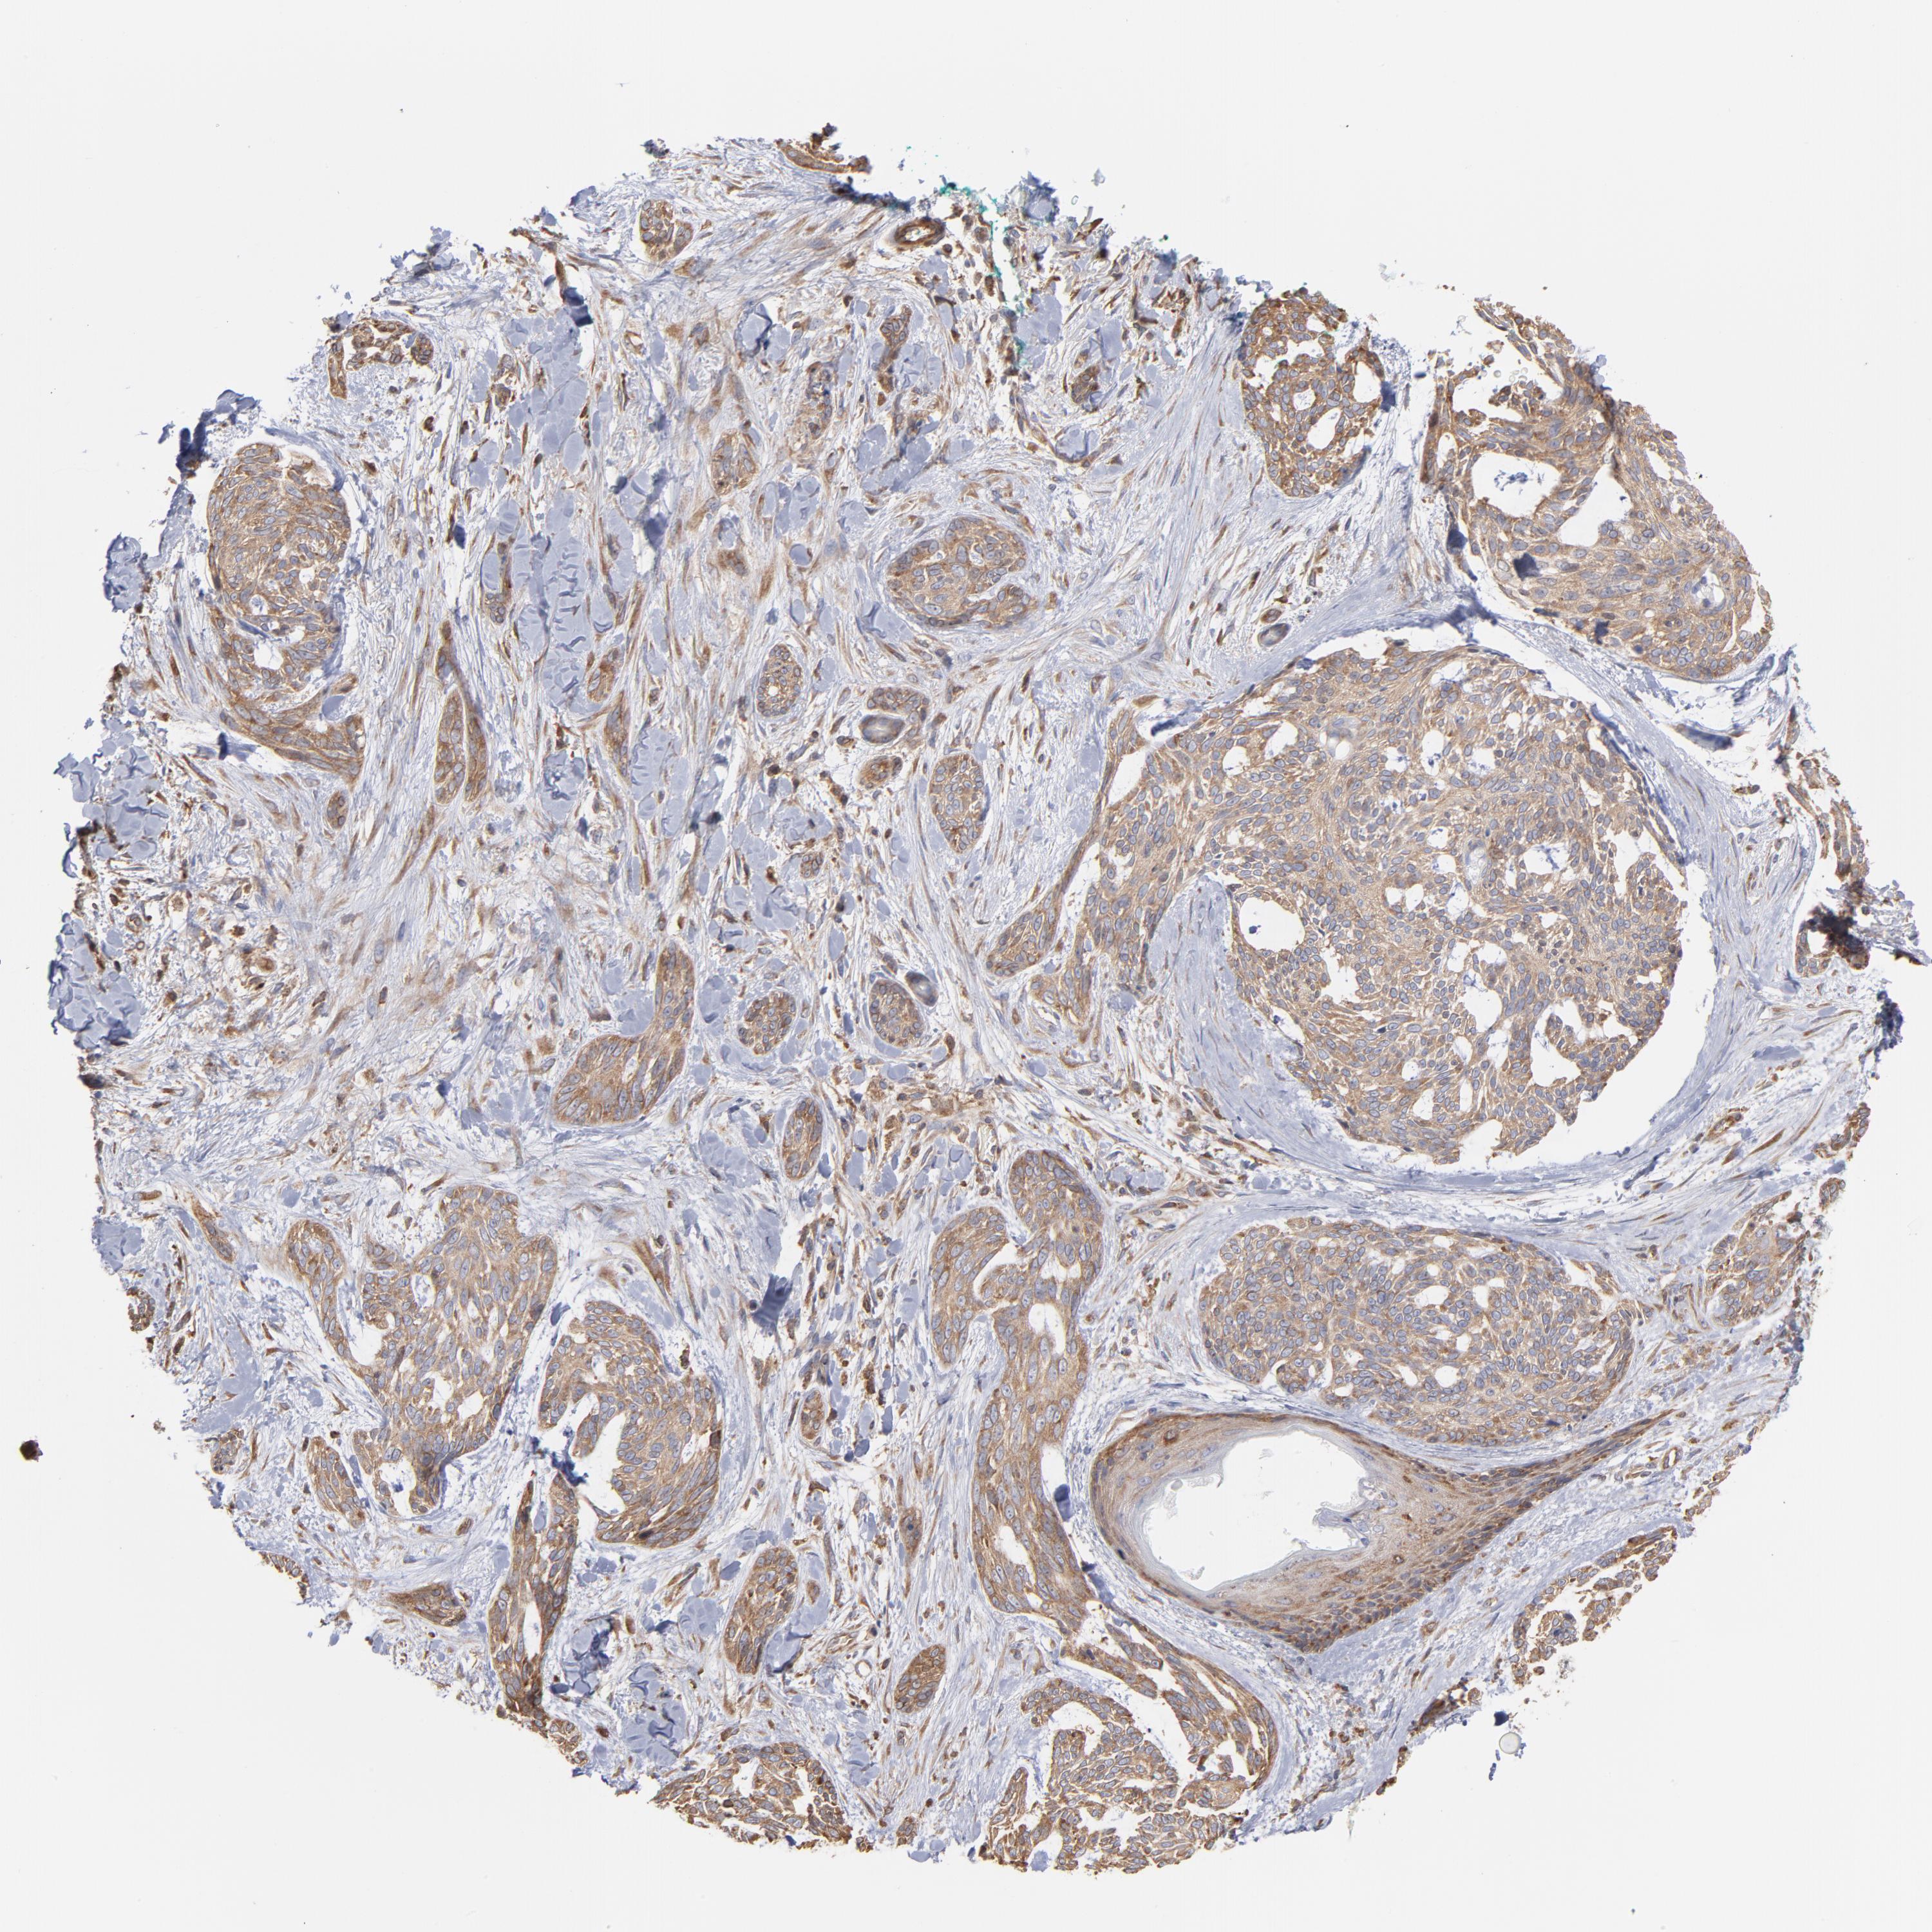

SKIN CANCER - Protein expressioni

A mouse-over function shows sample information and annotation data. Click on an image to view it in a full screen mode. Samples can be filtered based on level of antibody staining by selecting one or several of the following categories: high, medium, low and not detected. The assay and annotation is described here.

Antibody stainingi

Antibody staining in the annotated cell types in the current human tissue is reported as not detected, low, medium, or high, based on conventional immunohistochemistry profiling in selected tissues. This score is based on the combination of the staining intensity and fraction of stained cells.

Each image is clickable and will lead to virtual microscopy that enables deeper exploration of all samples and also displays staining intensity scores, fraction scores and subcellular localization as well as patient and tissue information for each sample.

Antibody HPA003600

Squamous cell carcinoma, NOS